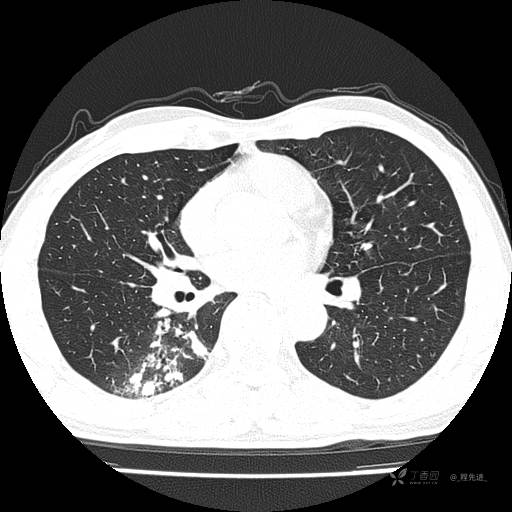

2月特别精彩病例|咳嗽、咳痰20余天,典型病例分享【结果已公布】

患者年龄:51岁

主诉:咳嗽、咳痰20余天

简要病史:20余天前开始出现咳嗽、咳痰症状,阵发性刺激性咳,白色粘痰,不易咳出,无发热,无咯血,无恶心、呕吐等不适,未诊治,咳嗽、咳痰症状持续存在。

体格检查:T:36.3 ℃ P:79 次/分 R:20 次/分 BP:128/64 mmHg,神志清楚,呼吸平稳,双肺呼吸音粗,右下肺闻及细湿性啰音。心率79次/分,节律整齐,各瓣膜听诊区未闻及病理性杂音。腹部未见异常,双下肢无水肿。

辅助检查:我院门诊胸部CT示:如下。心电图:窦性心律;正常心电图。